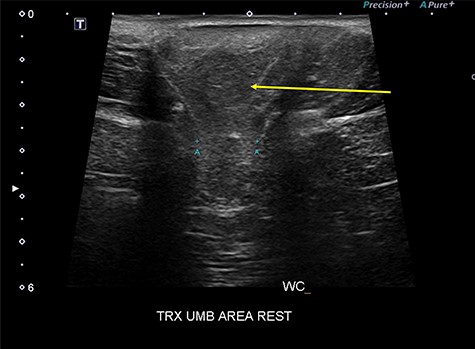

He did not smoke or lift heavy weights and his medical history was non-contributory. Radiological imaging in the form of an abdominal ultrasound described a fat lesion in the hernia sac (Fig. 1).

Abdominal wall ultrasound showing the one parietal peritoneal lipoma in the hernia sac (yellow arrow) and the 2 cm hernia neck (A-A).